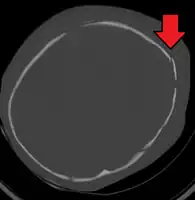

3D CT reconstruction showing a skull fracture in an infant